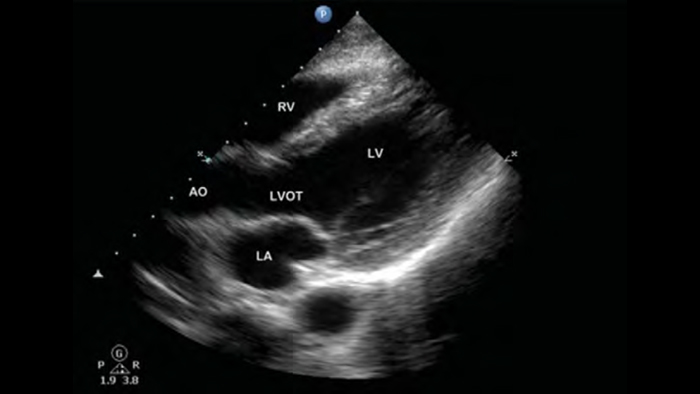

• Rango extendido de frecuencias de operación de 4 a 1 MHz • 2D, Doppler a color, Modalidad M, XRES avanzado e imágenes armónicas multivariables • Imagenología de alta resolución para aplicaciones abdominales y cardíacas: optimizaciones de preajustes de imágenes cardíacas, gineco-obstétricas, pulmonares, abdominales y FAST.

Desde revelar los detalles sutiles de una imagen hasta descubrir la definición del tejido enriquecido desde múltiples ángulos, Lumify puede ayudarlo a tomar decisiones en tiempo real con más confianza desde la evaluación hasta la recuperación.